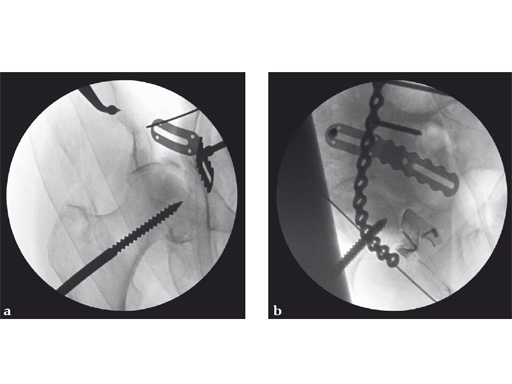

Fig 3ab AP hip and iliac oblique image intensifier views show initial quadrilateral surface plate placement with the aid of an asymmetrical clamp and subsequent introduction of overlying pelvic brim reconstruction plate. In this case a locking pelvic brim plate was chosen because of the severe osteoporosis.